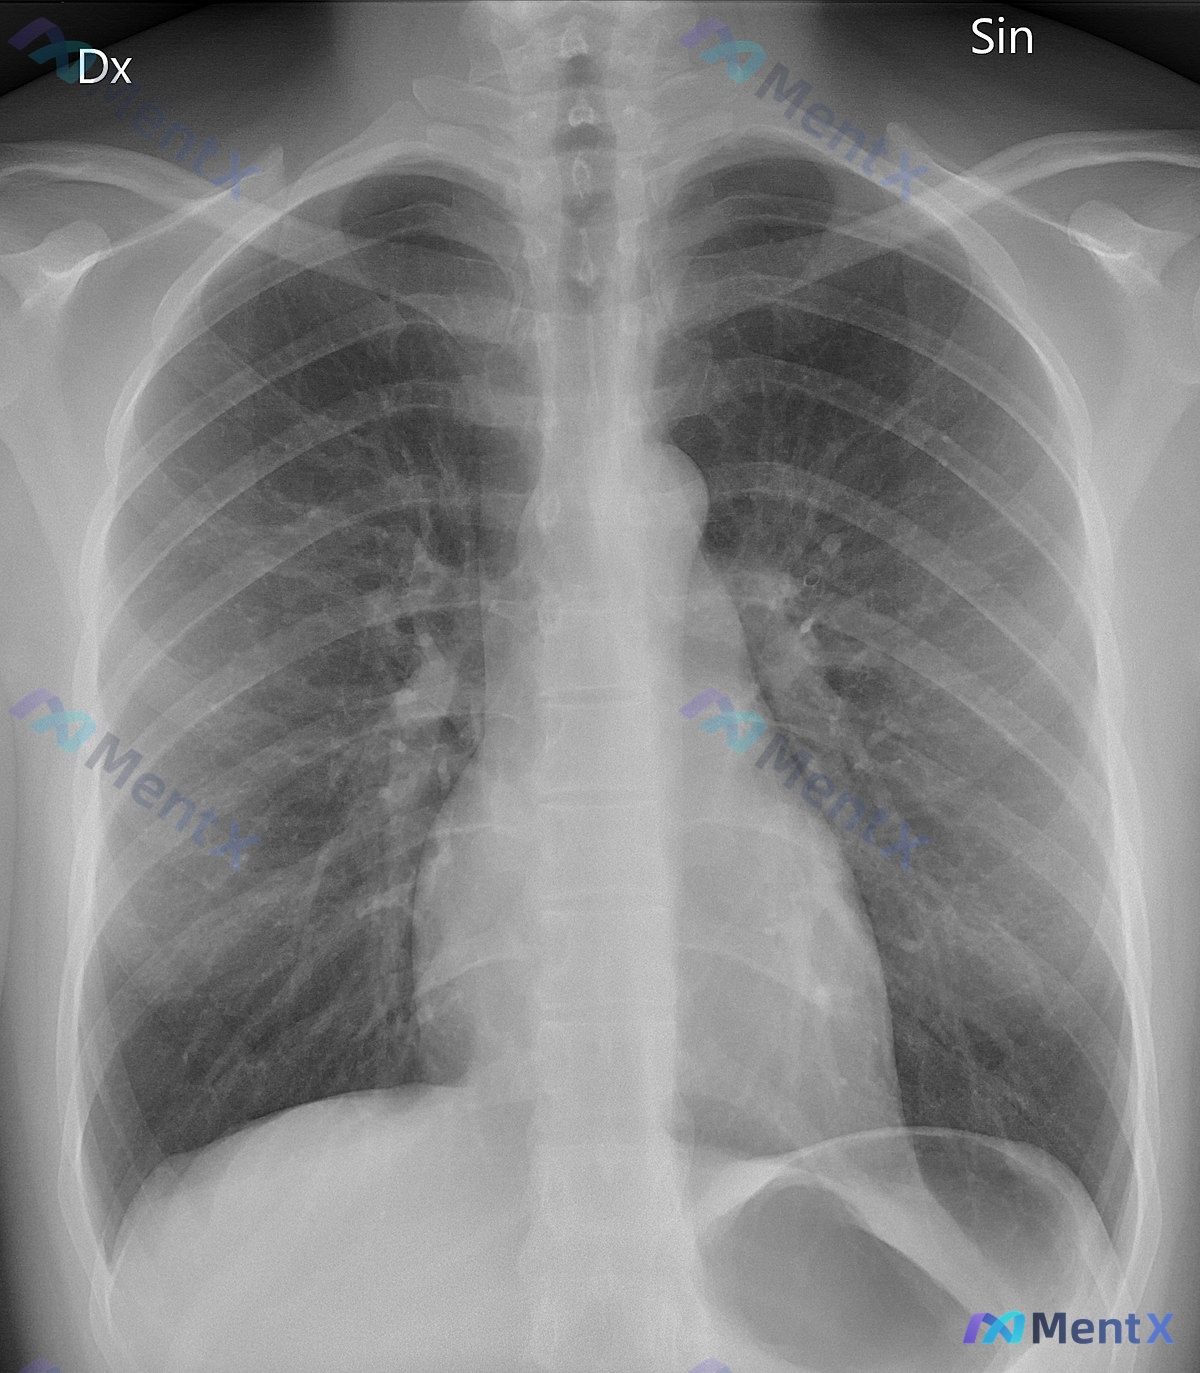

整理到一个84岁老年男性的病例资料,第一眼觉得容易漏,拿出来讨论一下。 基础情况:84岁男性,养老院居民,有阿尔茨海默病(无法提供病史),既往有冠状动脉疾病等。 就诊原因:跌倒后被送入预备病房,护理人员报告过去24小时疲劳程度加重。 查体与生命体征: - 体温 39.0℃ - 血压 82/65 mm...